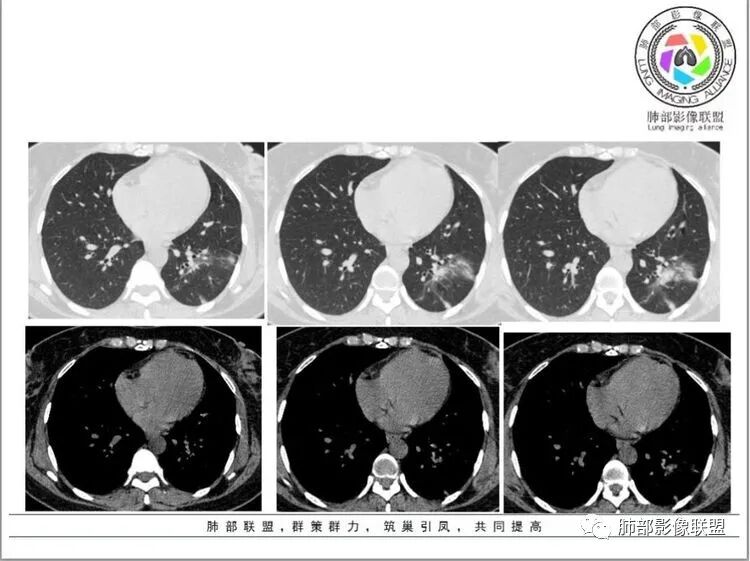

马春平(张家港市一院胸外科):

粘液腺癌>炎性病变

大病灶有重力感、小病灶有粘液飘出

蓝天白云:

左肺下叶条片状影,部分边缘有晕,似有坏死,可见纤细牵拉线,内见支气管通行,临床咳嗽咳痰两个月,考虑炎性病变,隐球,鉴别粘液腺癌

田园晚风:

同意腺癌,女性,咳粘液白痰也符合,有牵拉,有磨玻璃,有空泡

隐球菌

1.中年女性,亚急性病程,以咳嗽、咳痰、胸痛为主。

2.左肺下叶胸膜下团片影及多发小片影,团片影长轴与胸膜平行,周围有模糊的晕,局部平直收缩,支气管近端堵塞,病灶内可见小空洞,空洞内壁光整,邻近胸膜牵拉。

结合肿块周围有多发小片、结节影等类似形态的卫星灶,病灶像炎性,没有游走性,但长时间段抗炎治疗无效,应当想到特殊感染的可能,如隐球菌感染或其他慢性炎症,如结核等。

注意,隐球菌感染出现胸痛的不在少数,敬请留意。

3.患者丈夫有肺结核病史,理应考虑肺结核可能性,但患者病灶周围没有典型树芽,而且病灶的形态较为单一,分布特点都不大符合典型的结核影像学特点。